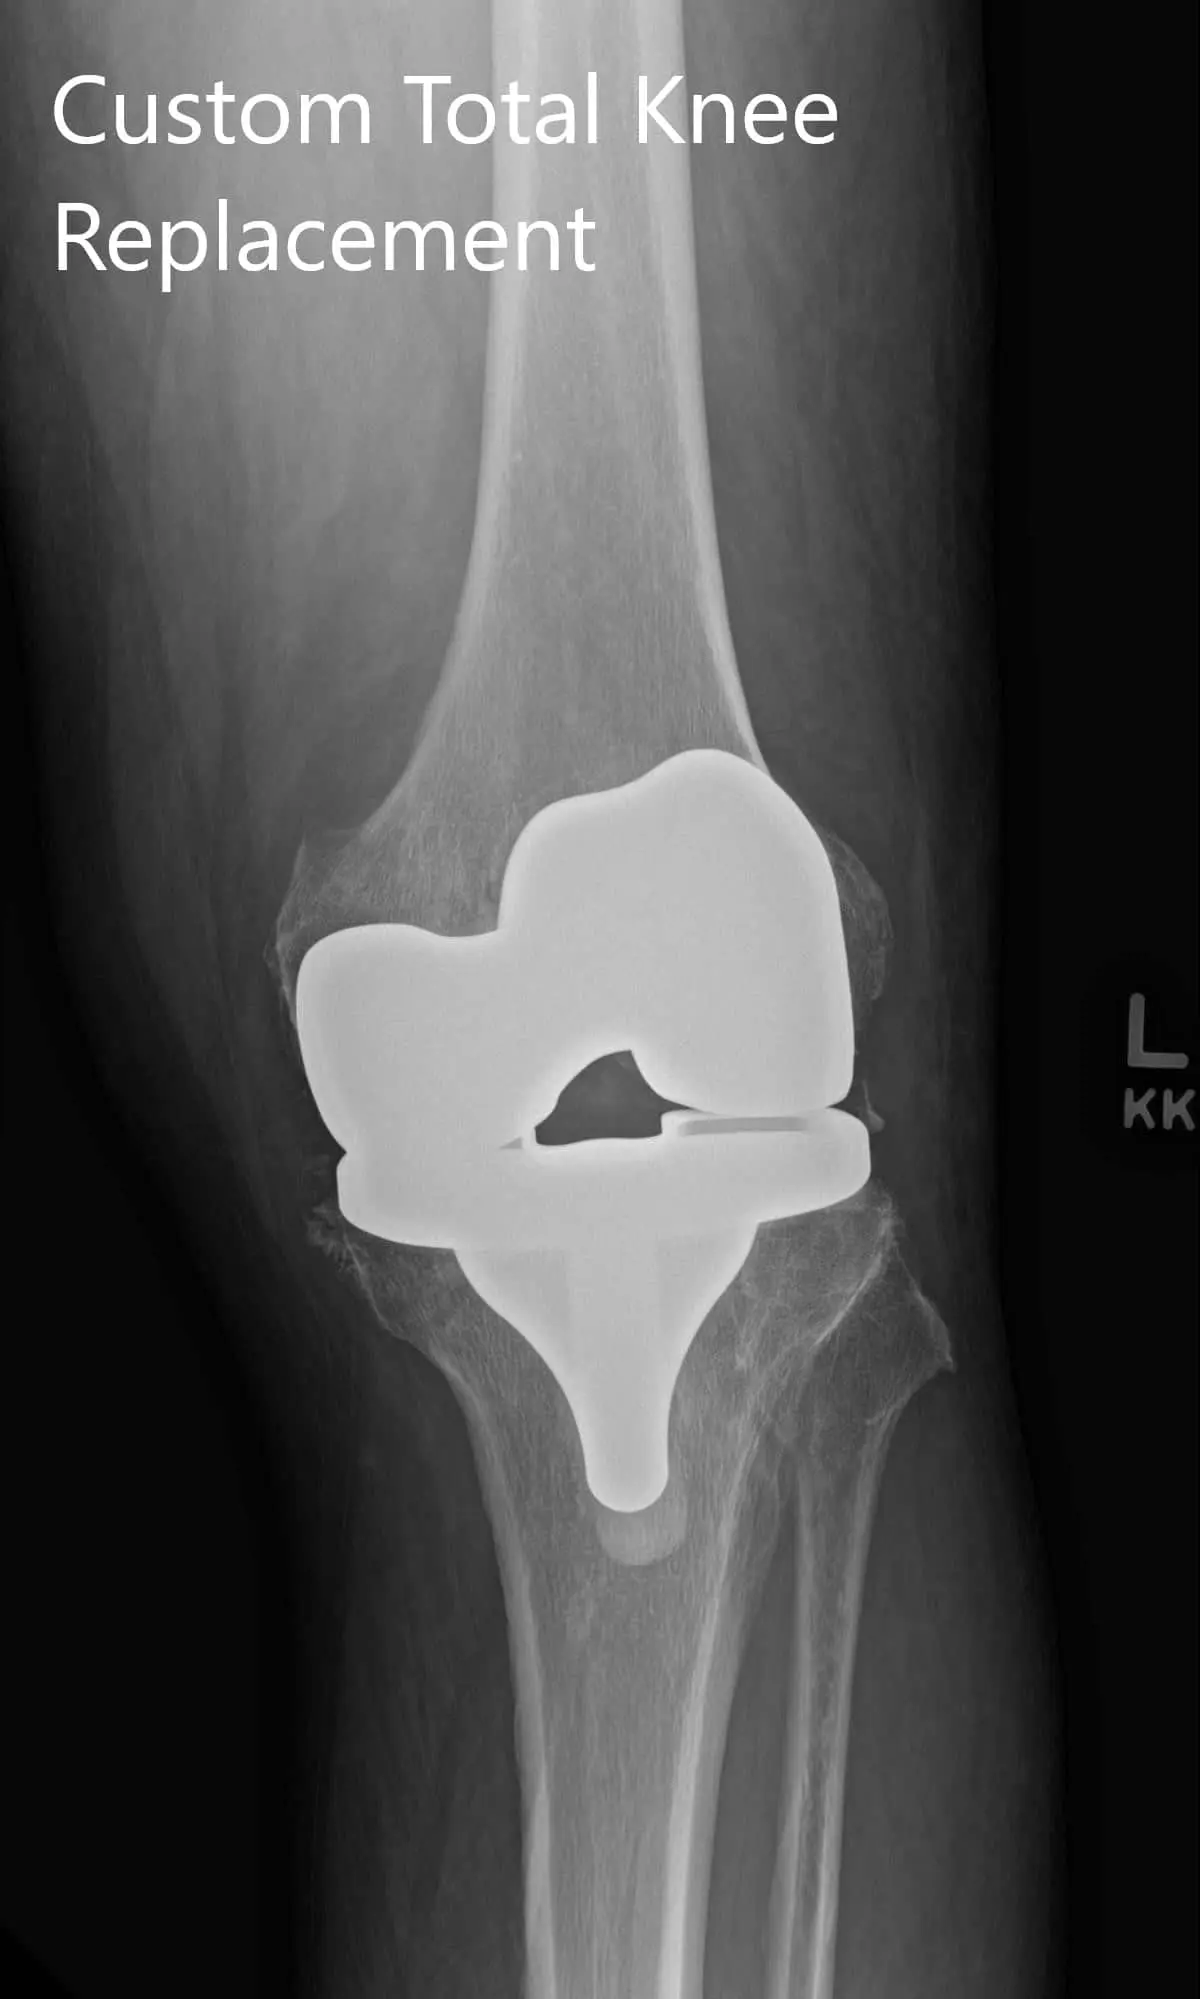

Postoperative X-ray showing AP and lateral images of the left kneePostoperative X-ray showing AP and lateral images of the left knee - img 2

Postoperative X-ray showing AP and lateral images of the left knee.